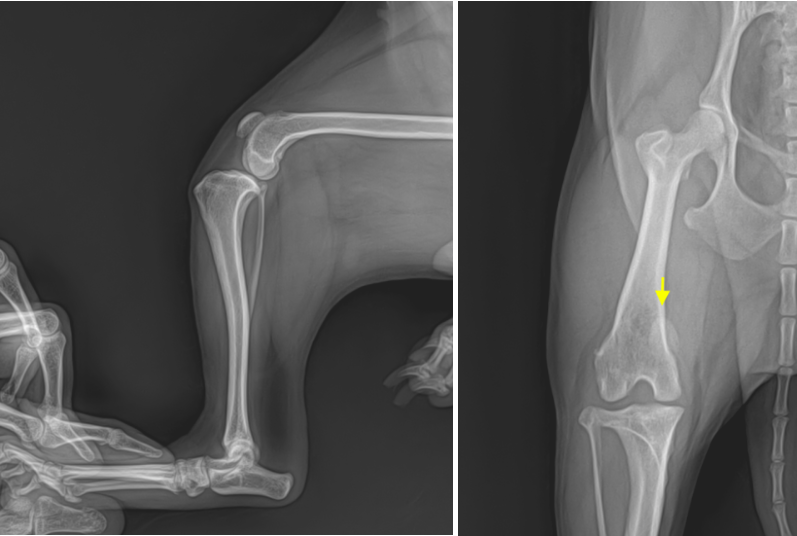

에스동물메디컬센터 양산점에서는 십자인대 파열 정확한 진단을 위해 신체검사, 무릎관절 X-ray, 전방 전위 검사를 진행하였습니다. 전방 전위 검사는 무릎 관절의 불안정성을 평가하는 검사로 십자인대 단열을 검사하는데 유용합니다.

■ X-ray 검사 결과

종합적으로 우측 슬개골 탈구 및 전방 십자인대 완전 파열(CrCL rupture)로 확진하였습니다.

양산 에스동물병원 강아지 슬개골탈구 X-RAY 사진 / 출처: 에스동물메디컬센터